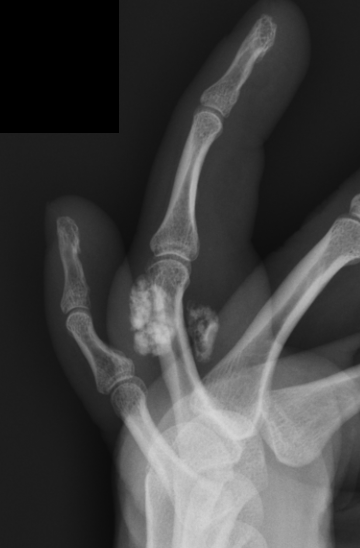

X-ray

Well defined bony mass arising from the surface of the bone

- no medulla

CT

Lesion not continuous with adjacent with cortex

- no cartilage cap